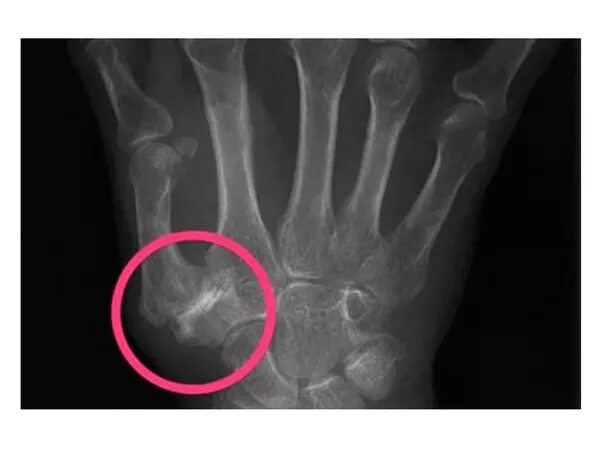

Артроз запястно пястного сустава